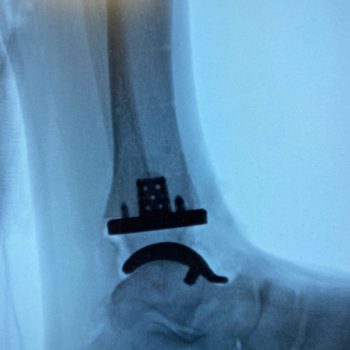

Exactech’s Vantage Ankle 3D and 3D+ tibial implants provide surgeons with tibial stem heights from 10 to 30mm and the added benefits of 3D printing. Additive manufacturing creates a surface that mimics the trabecular nature of cancellous bone. Along with the 3D-printed surface, the implants also feature spiked pegs and a tall sharp central cage, with growing diameters, to aid with initial fixation.

“After several years of developing the 3D+ tibial component with the outstanding Exactech engineers and other design team surgeons, Jim, Jim [Lachman] and I are pleased how the new tibial components and instrumentation seamlessly melded with the existing talar component options. The additive manufacturing, and the press-fit pegs and augmented central cage afford satisfying initial tibial component stability. Particularly exciting is how the intuitive instrumentation allows for reliable and reproducible insertion of a stemmed tibial component through a routine anterior ankle surgical approach.”